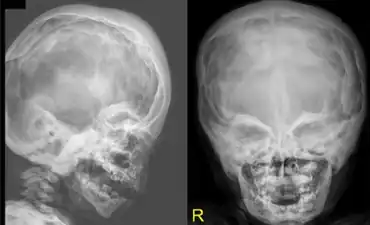

Craniodiaphyseal dysplasia (CDD), also known as lionitis, is an extremely rare autosomal recessive bone disorder that causes calcium to build up in the skull, disfiguring the facial features and reducing life expectancy.

These calcium deposits decrease the size of cranial foramina, and can decrease the circumference of the cervical spinal canal. In the few cases recorded, most of the sufferers died in childhood.

- Craniofacial hyperostosis

Among the medical signs are dacryocystitis, seizures, intellectual disability, and paralysis, each of which is a complication resulting from the diminutive foramina. A common sign reported as a result of the disease has been widely spaced eyes.[4]